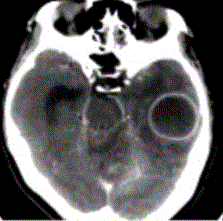

问题 患者女,26岁,头痛、低热10d余,既往有左侧慢性中耳炎病史。CT表现如下图。 MRI检查中,脑脓肿最敏感的方法或序列显示是

选项 A.T2*WI B.DWI C.FLAIR D.T2WI E.PDW

答案 B